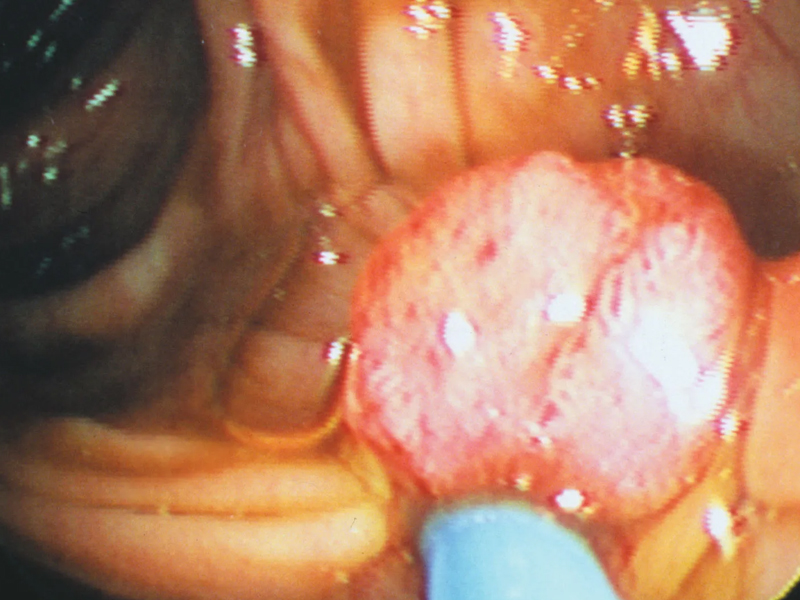

瀏覽:34125 肺部有癌,雙腳先知?同時出現 4 現象,癌症或已到了中晚期 | 瀏覽:11843 體內有癌,肛門先知 | 瀏覽:5444 別不當回事!這 6 種小病,很多人最後拖成了癌 |